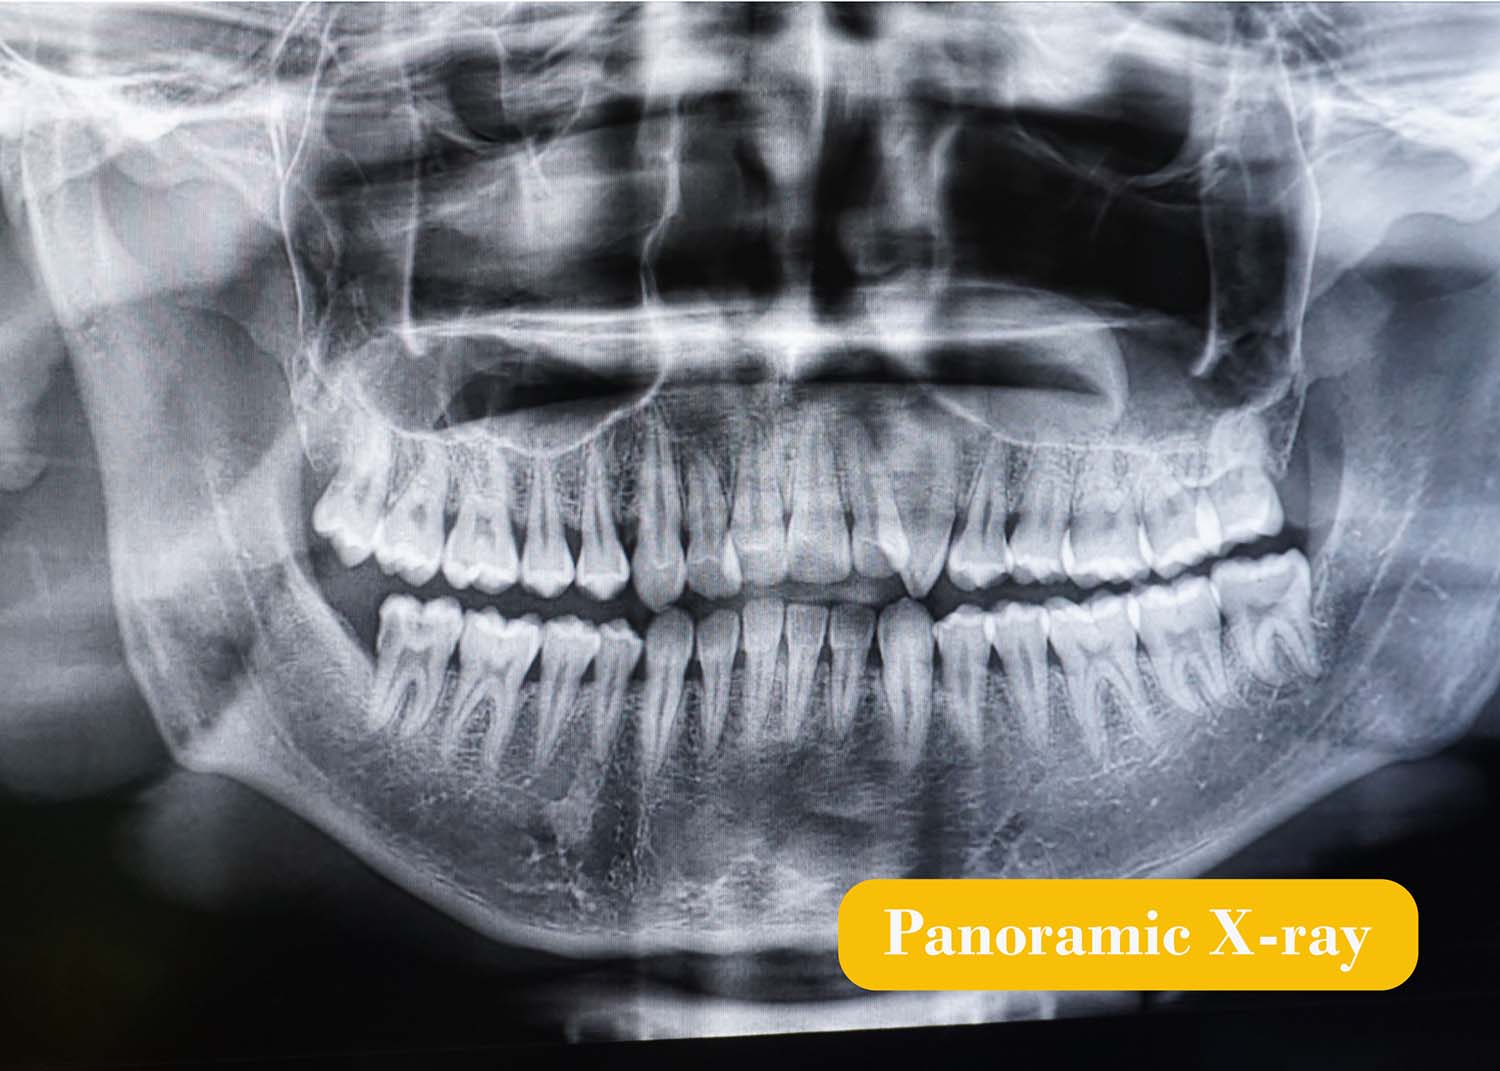

Panoramic digital X-ray